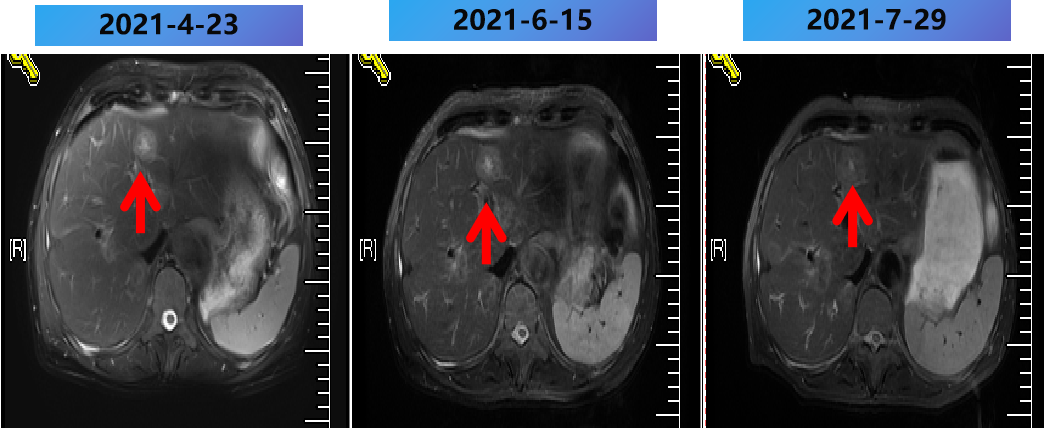

2021-2-25至2021-7-15 更换方案为bev+伊立替康+雷替曲塞 9周期,部分病灶稳定(SD)。

2021-2-25至2021-7-25 更换方案为bev+伊立替康+雷替曲塞 9周期,部分病灶PD。